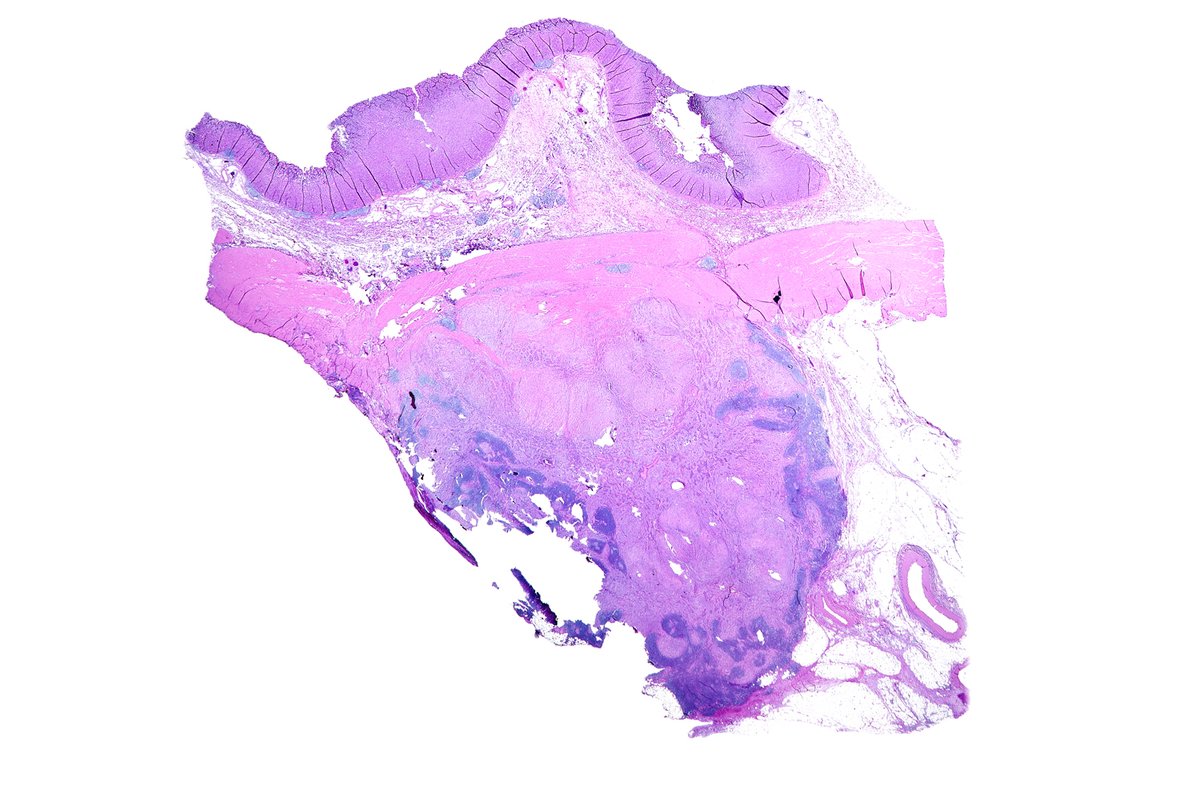

34 year old female abdomen, sent in as cyst #dermpath David Terrano Mariantonieta Tirado Allison Osmond MD MSc FRCPC Dermpath_doc_trish Henry YANG Olaleke Folaranmi Pathology Jerad Gardner, MD Christine J. Ko, MD Lorand Kis James Sampson American Society of Dermatopathology #BSTPath